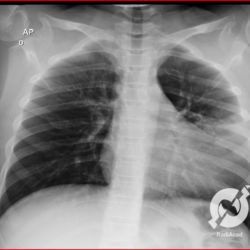

Os agentes etiológicos infecciosos são variados (bactérias, vírus, fungos, parasitas…), mas o que ocorre nos pulmões durante uma infecção por qualquer tipo de agente é a substituição do ar alveolar por secreção (pus, muco, eventualmente sangue ou necrose…) e com isso a manifestação radiográfica vai ser a mesma já que todas estas secreções apresentam a mesma densidade radiográfica: partes moles.

E o nome dado a esta alteração radiográfica que corresponde à substituição do ar alveolar por líquido é a consolidação alveolar.

Uma consolidação alveolar é, por definição, uma opacidade (imagem densa, branquinha) homogênea ou às vezes heterogênea (pela presença de calcificações ou cavidades), de limites mal definidos, exceto quando toca a pleura da parede ou das cissuras pulmonares. É um termo usado tanto em radiografia, como em tomografia computadorizada. Na tomografia, um outro termo é usado: vidro fosco, que é uma opacidade (branquinha mas não tanto como a consolidação), que borra o pulmão mas deixa ver os vasos de permeio (igual bigode de adolescente: dá pra ver todo o fundo).

Nós vamos mostrar aqui um pequeno apanhado de pneumonias de variados agentes, em diversos segmentos e lobos pulmonares, com extensões variadas. O objetivo é identificar o padrão radiológico de consolidação alveolar e não determinar o agente infeccioso, isso vai ser assunto para mais adiante. Aliás já antecipo que é fundamental saber localizar a lesão, porque alguns destes bichos gostam de determinados segmentos, alguns tumores também têm as suas preferências, então localização é fundamental. Se localização não fosse importante, um apartamento na beira do mar sairia o mesmo preço de um apartamento de frente pra BR-101, concordam?

Seguem alguns dos nossos casos de pneumonia para vocês treinarem os olhos e não se apavorarem nos plantões.